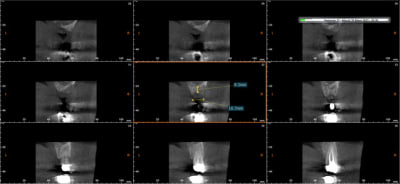

pour la petite histoire le scan me montrait une hauteur a 7.5 mm au dessus de nerf et a la retro on a l'impression qu'il reste des kilomètres.

Un cas avec un peu plus d'un an d'ostéointégration

6X5 Biocom MIS

Non enfoui, mis en charge a 3 mois en face il y a une arcade dentée...

c'est sur si on perd des spires ça va aller vite, mais alors on fera un sinus...

pas facile de trancher entre complication sinus/implant court...